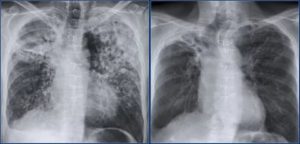

После успешной терапии туберкулеза медикаментами функция легких продолжает ухудшаться. Очаги воспаления уплотняются, пораженные ткани заменяются рубцами и кальцификатами. Метатуберкулезные изменения могут протекать без симптомов или ухудшать дыхательную функцию.

На рентгенограмме метатуберкулезный пневмосклероз проявляется затемнениями или светлыми очагами, которые находятся в бронхолегочной системе, плевре и средостении.